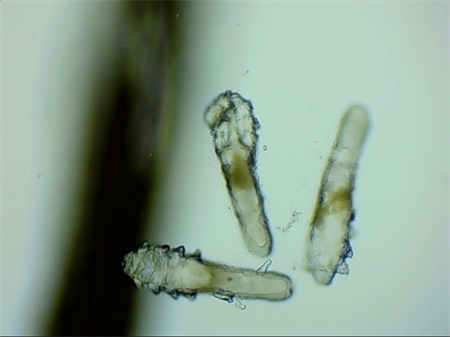

這就不得不提到眼科醫(yī)生經(jīng)常使用的螨蟲檢測(cè)工具——螨蟲鏡檢。它通過顯微利器,無死角全方位掃描你的睫毛,讓螨蟲無處遁形。

▲螨蟲鏡檢